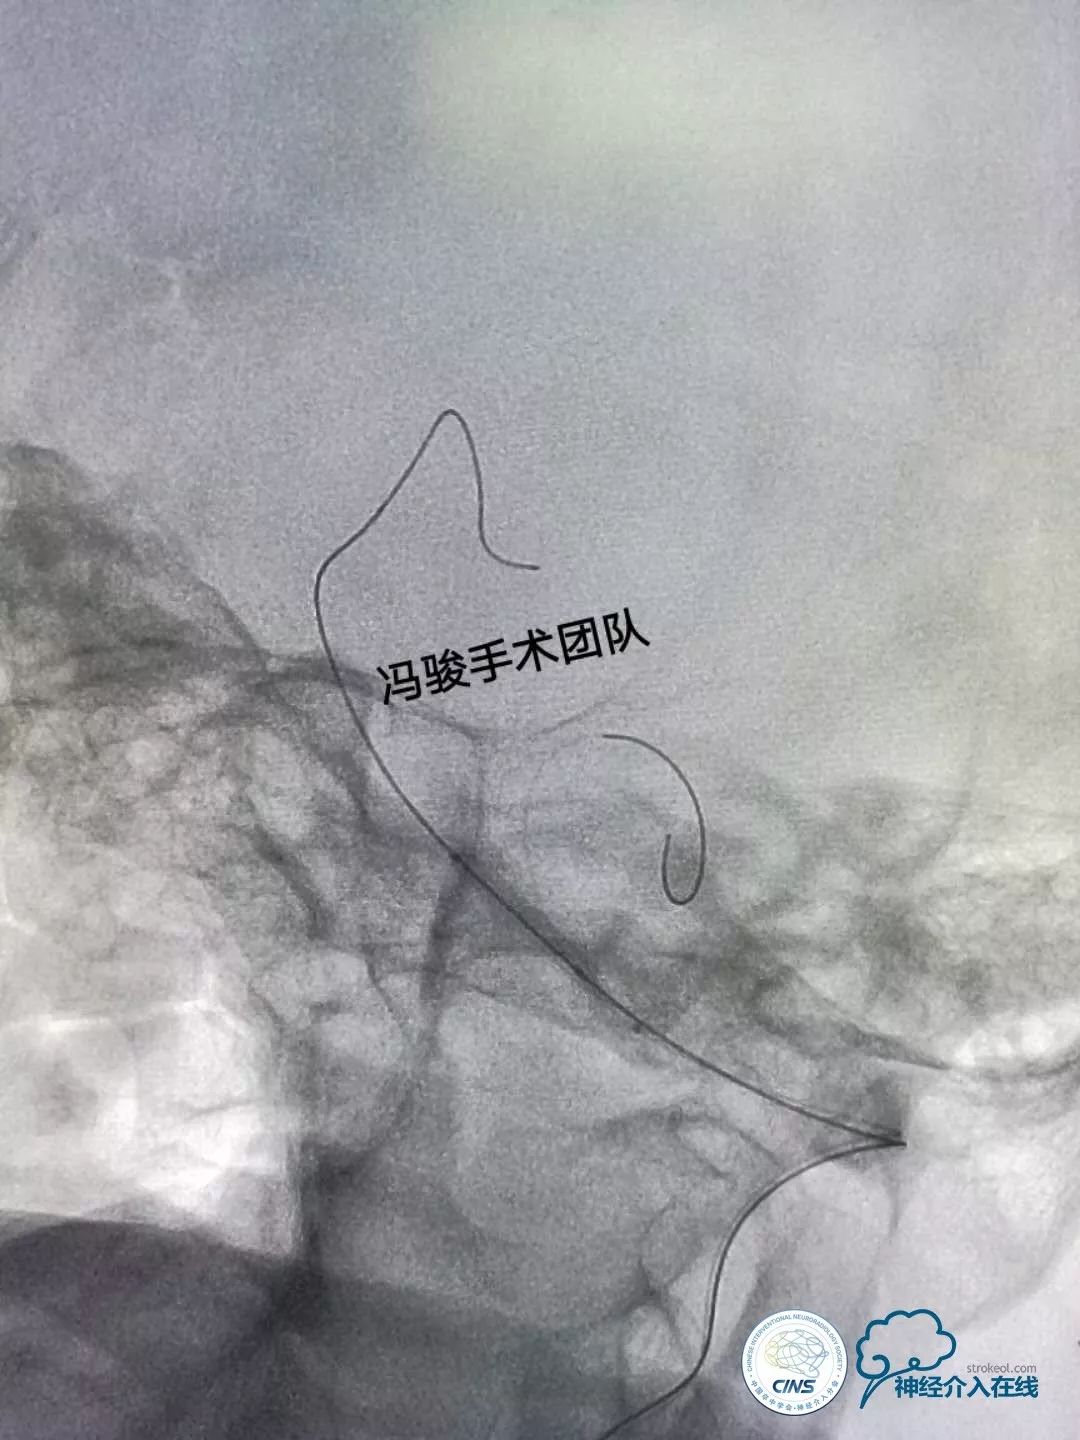

全麻下,将6F的envoy通过左椎动脉V1迂曲段,置于V2段远端,使用双导丝保护技术,1根微导丝置于左侧大脑后动脉,另1根置于左PICA。